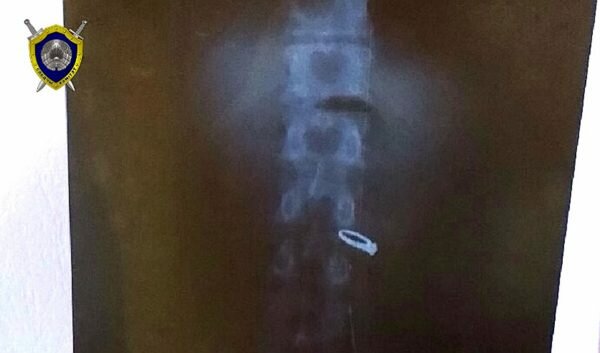

Гостившего у жительницы Верхнедвинска мужчину задержали в Полоцке, но он упорно отрицал свою причастность к краже кольца. Но во время медицинского освидетельствования, врачи с помощью флюорографии обнаружили, что пропавшее кольцо находится у него в желудке.

Кольцо уже извлекли, его осмотрели и признали вещественным доказательством, а потом отправили на экспертизу. После этого обвиняемый дал признательные показания.